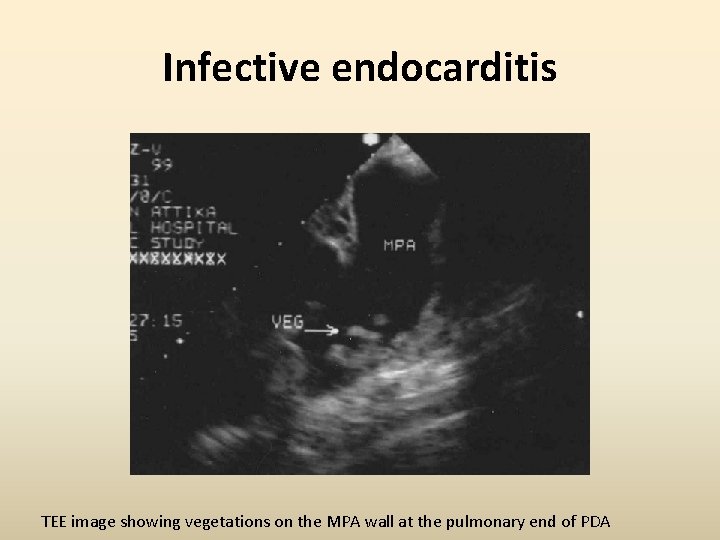

Infective endocarditis TEE image showing vegetations on the MPA wall at the pulmonary end of PDA